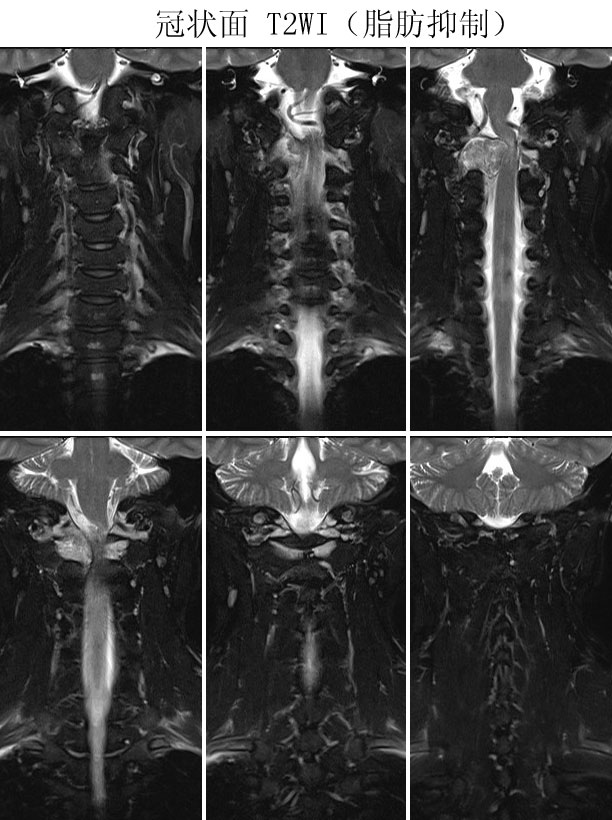

本病例来自广东同江医院

病史:女,27岁,洗头按摩时扭颈导致昏迷,检查发现颈椎占位

手术病理:

神经鞘瘤